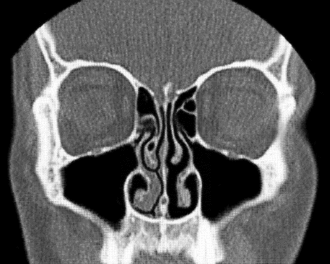

Frontalschnitt einer Computertomographie der Nasenhöhle und Nasennebenhöhle -